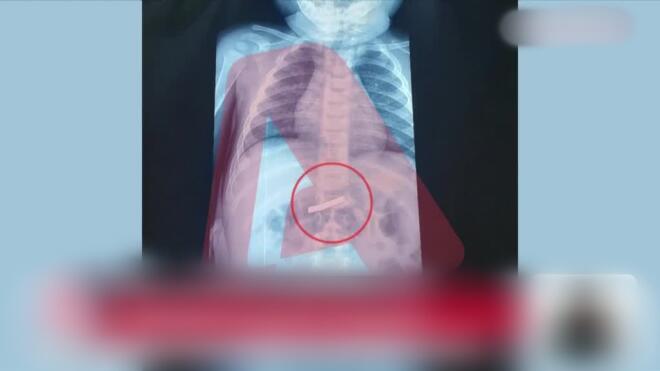

Του έγιναν αμέσως οι απαραίτητες εξετάσεις και ακτινογραφία, η οποία έδειξε ότι το παιδί είχε καταπιεί το αιχμηρό αντικείμενο. Οι γιατροί διαπίστωσαν ότι είχε φτάσει στο στομάχι του 3χρονου και έκριναν απαραίτητο να γίνει άμεσα χειρουργική επέμβαση.

Σύμφωνα με πληροφορίες που μετέδωσε ο Alpha, το αγοράκι υπεβλήθη σε χειρουργείο και το αντικείμενο αφαιρέθηκε με επιτυχία, με το παιδί να έχει διαφύγει τον κίνδυνο.